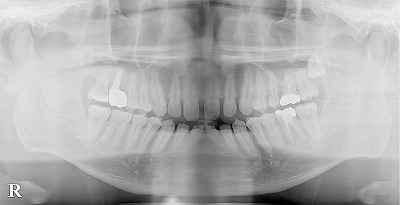

デンタルドック(歯科検査) 歯が原因の蓄膿(歯性上顎洞炎)の治療について 2025.05.18 LINE note Post Share Hatena LINE RSS feedly Pin it note この記事のタイトルとURLをコピーする 副鼻腔炎の歯科インプラントによる治療、予防治療、再建治療 前の記事 部分歯列矯正、レーザー、歯を削らないセラミック治療による前歯の審美歯科治療 次の記事